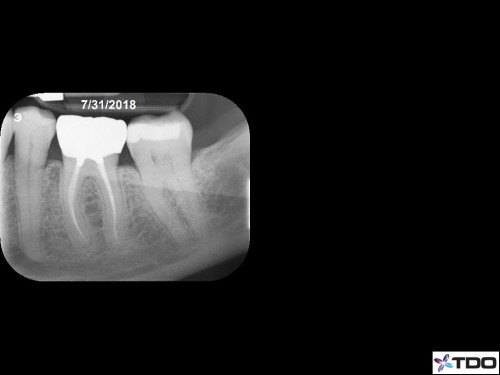

Another 6-Month Follow-up

From last week. 59yof. SIP. Hyperemic. 6 canals. 2 visits. Asymptomatic at the second visit. Asymptomatic and functional at the follow-up appointment.